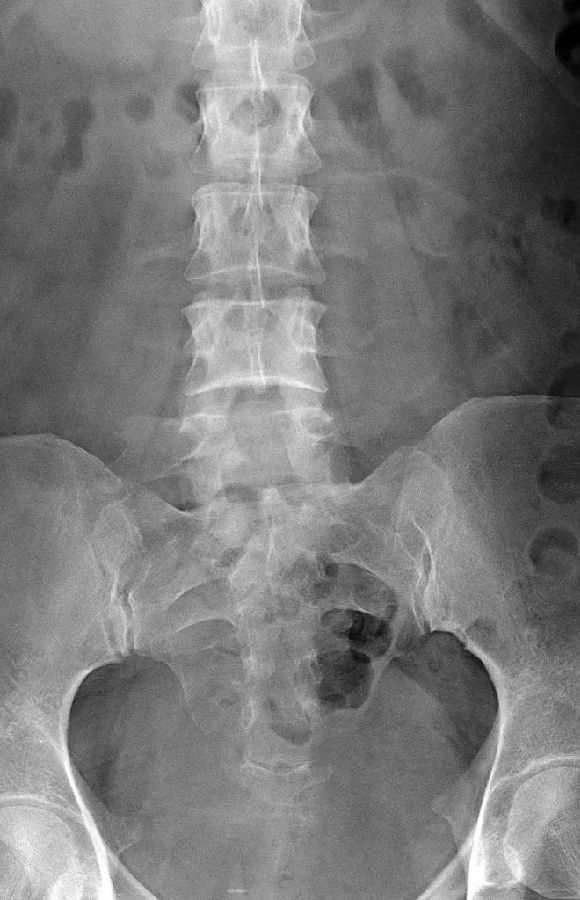

腰椎骶化及骶椎腰化均是椎骨发育的异常,腰椎骶化是指第五腰椎外型类似骶椎形态,并构成骶骨块的一部分,一侧或两侧横突肥大呈翼状,与骶骨发生融合或形成假关节。骶椎腰化是指第一骶椎演变成腰椎样形态,即第一骶骨从筋骨块中游离出来形成第6个腰椎。

如何在临床阅片准确判断是一个很重要的问题,这里介绍一个最准确的判断方法。

这是一个最关键和准确的鉴定方法,国内著名骨放射学家杨世埙教授指导过,只要大家留意关注腰椎横突"三长/四翘/五宽",L3横突是最长的,L4横突是上翘的,L5横突最宽,特别用在胸椎腰化合并L5骶化的时候比较实用。

它与腰骶部疼痛存在密切的相关性是不可忽视的,并干扰诊断与之症状相近的其它疾病,如椎间盘突出、致密性骨炎、强直性脊柱炎等等,当然这其中有些疾病可以并存,X线、CT检查在腰骶部移行椎的诊断中有重要意义,不仅能对本病做出诊断,并且有助于鉴别诊断。